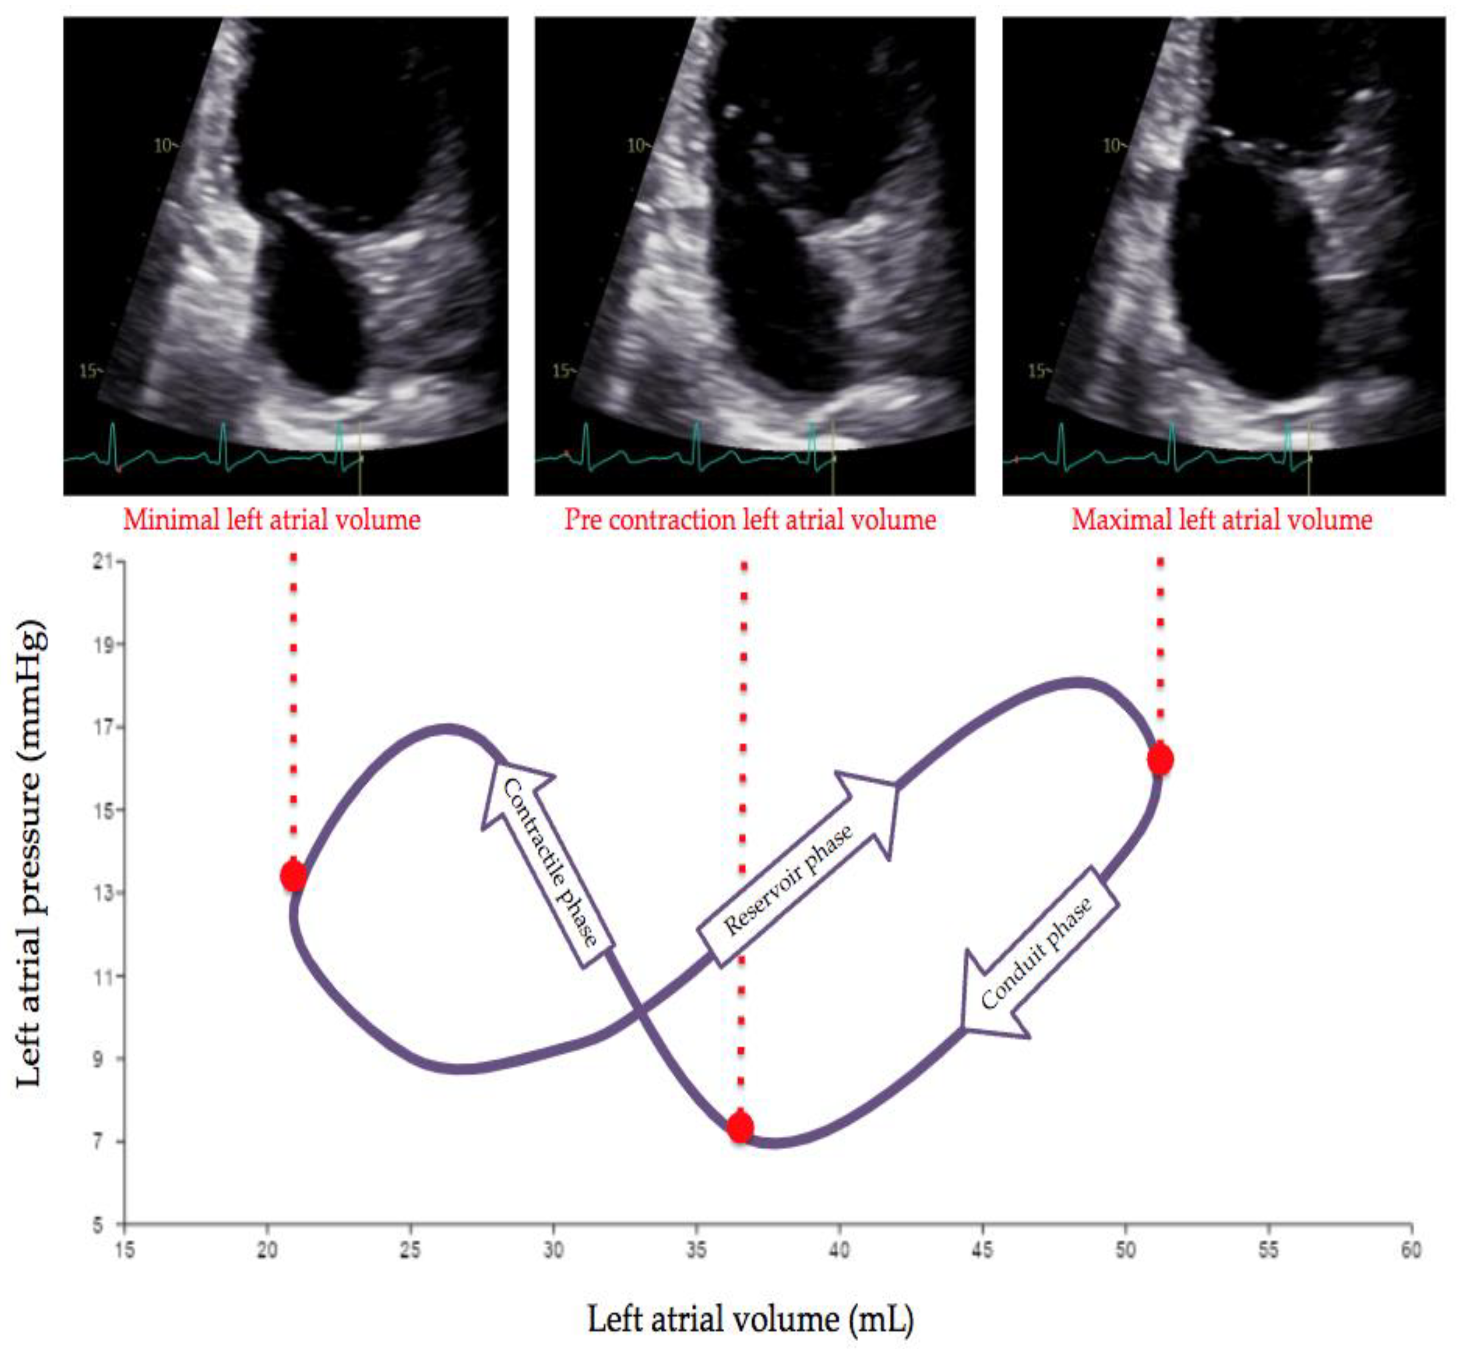

| LA Function | Functional Parameter | Calculation |

|---|---|---|

| Global function | LA EF | (LAmax − LAmin)/LAmax |

| Reservoir function | Expansion index | (LAmax − LAmin)/LAmin |

| Conduit function | Passive EF | (LAmax − LApreA)/LAmax |

| Booster pump | Active EF | (LApreA − LAmin)/LApreA |